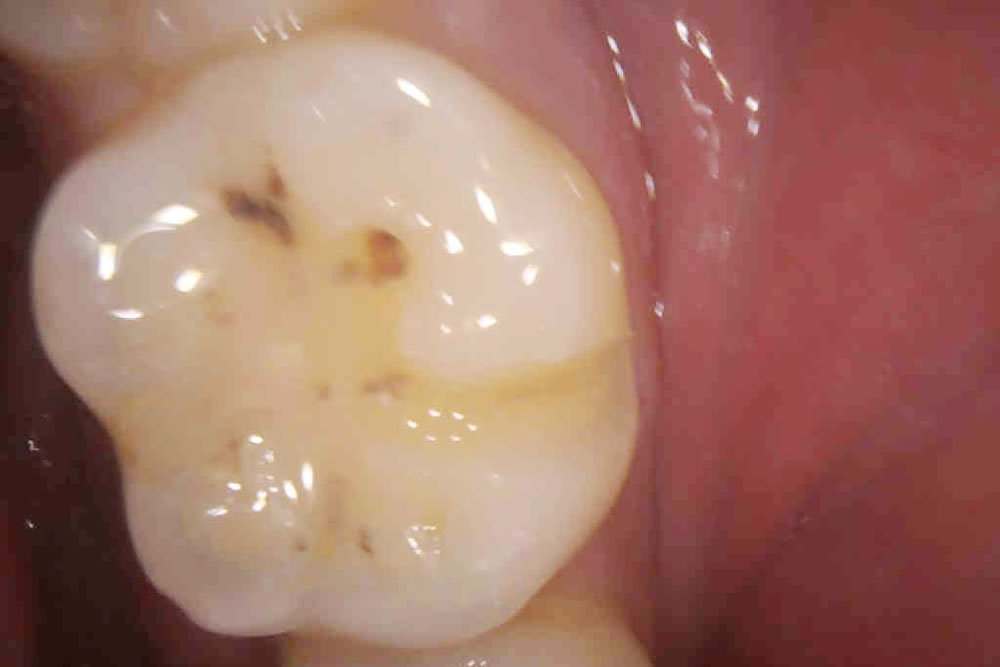

むし歯治療